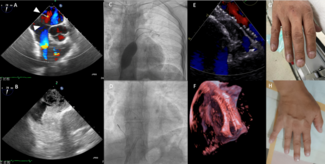

Katia Librandi, MD; Mohammad Abumehdi, MD; Andreas Hoschtitzky, MD; Thomas Semple, MD; Rodney Franklin, MD; Alain Fraisse, MD, PhD

The authors report a late-diagnosed APW in a 4-year-old male with high pulmonary arterial pressure and high pulmonary vascular resistance index who was initially treated with transcatheter device closure as a bridge for surgical repair.

05/30/2024

Konstantinos Antoniades, MD; Sotirios C. Kotoulas, MD; Dimitrios Iliopoulos, MD; Efthymia Koutsogiannaki, MD; Aimilianos Kalogeris, MD; Leonidas E. Poulimenos, MD; Andreas S. Triantafyllis, MD, PhD

A 59-year-old diabetic man with a history of numerous coronary angiographies (CAs) and peripheral artery disease underwent CA due to a non-ST elevation myocardial infarction. Femoral, radial, and ulnar arteries were unpalpable.

Cheuk Bong Ho, MBBS; Ivan Wong, MBBS; Michael Chi Shing Chiang, MBBS; Angus Shing Fung Chui, MBChB; Alan Ka Chun Chan, MBBS; Chi Yuen Wong, MBBS; Kam Tim Chan, MBBS; Michael Kang Yin Lee, MBBS

Cheuk Bong Ho, MBBS; Ivan Wong, MBBS;...

A 63-year-old man presented with delayed inferior ST-elevation myocardial infarction complicated with ventricular septal rupture. He developed cardiogenic shock and respiratory failure requiring intubation and Impella (Abiomed) support.

Marco Alejandro Solórzano Vázquez, MD; Fernando Donovan Espriu Romero, MD; Edgar Uriel Quintana Ortiz, MD; Oscar Samuel Medina Torres, MD

Marco Alejandro Solórzano Vázquez, MD...

A 37-year-old man was referred to our medical center with a diagnosis of Eisenmenger syndrome due to an atrial septal defect (ASD). At admission he had central cyanosis, acrocyanosis, and progressive effort dyspnea; his symptoms improved...